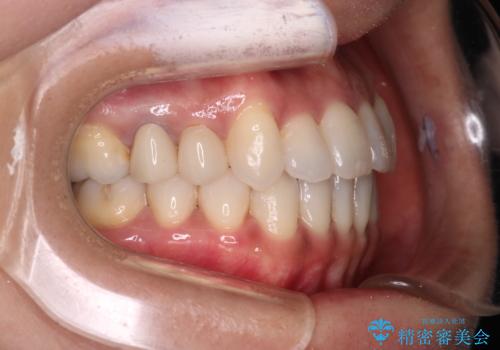

【審美装置】抜歯の本数最小限で行った矯正治療

- 治療計画

- 全体のがたつきを主訴に来院されました。4番目の歯を4本抜歯も検討しましたが、口元が下がりすぎてしまうリスクと2番目の転位うが著しく並べるのにかかる期間を考慮し、変則的な抜歯をし、並べる計画を立てました。

抜歯矯正のため2年はかかってしまいましたが、きれいに並び患者様にも満足頂きました。